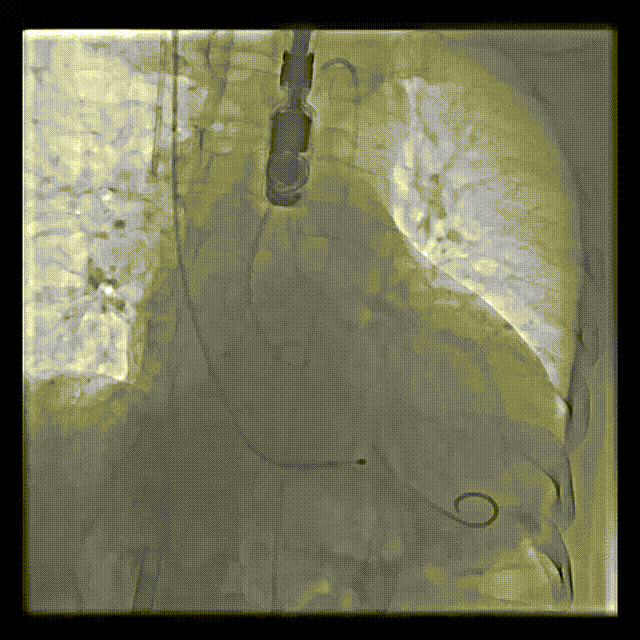

主动脉根部造影